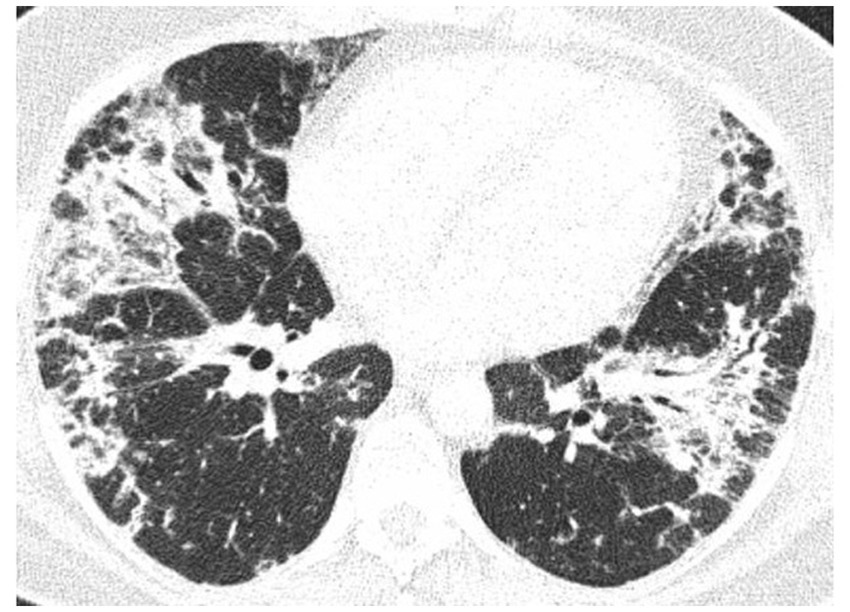

Chest computed tomography

High-resolution computed tomography (HRCT) is the gold standard in the evaluation of OP. It reveals multifocal areas of consolidation, often with a characteristic air bronchogram. Additionally, patchy alveolar consolidations, nodules, areas of ground glass opacity, perilobular infiltrations, bronchial wall thickening, and reticular fibrous changes may be present in peripheral parts of both lungs. Thickening around areas of ground glass opacity with an “atoll” or “crazy-paving” pattern may also be present, although it is less common. Additionally, nodular lesions, pleural thickening, and rarely enlargement of hilar and mediastinal lymph nodes, are present; emphysema or pleural effusion may also be observed (28–40). Honeycomb-type lesions are not in the spectrum of pulmonary changes observed in COP but might be evident in patients who exhibit interstitial pulmonary fibrosis with a component of OP (Figures 2–6).

Figure 2

High resolution computed tomography scan of a patient with COP. Bilateral ground glass opacities with associated peripheral consolidations forming an atoll sign.